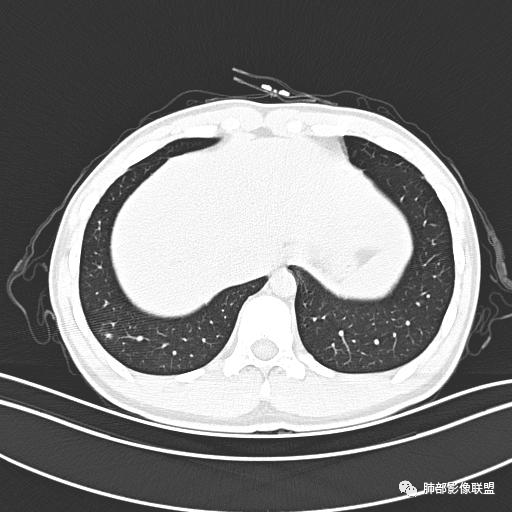

小强:青年,发热,皮疹;双肺散在结节,周围磨玻璃,点晕征,疱疹病毒感染,鉴别荚膜组织胞浆菌,结核。 大雄:青年,急性起病,发热伴全身皮疹2天,抗病毒治疗体温有下降。双肺随机分布大小不等类圆结节,“点晕征”。考虑水痘-疱疹病毒(VZV)血播询问接触史,查体皮疹分布以及形态基本可诊断。 王开金江津中心医院呼吸科:青年男性,起病急,病程短,以发热,皮疹为首发症状,感染指标以单核细胞升高为主,胸部ct双肺多发结界,周围有晕,点晕表现,随机分布,同意於老师意见,水痘疱疹病毒血流感染累及肺。 王秀仙:双肺多发大小不等结节,周围有晕,边缘模糊,呈点晕征表现。青年,急性起病,发热伴全身皮疹2天,抗病毒治疗体温有下降。考虑疱疹病毒。鉴别荚膜组织胞浆菌。 傅昌瑜:19岁男性,发热、全身皮疹2天,单核细胞增高,双肺多发结节,结节边缘见边界不清磨玻璃影。点晕征+发热、全身皮疹+单核细胞增高——考虑水痘-带状疱疹病毒肺炎。 一切∮随缘:年轻男性,发热,皮疹两天,实验室,CRP,PCT增高,影像:双肺多发散在磨玻璃结节,边界欠清,大小不等,呈点晕征改变,以血管束周围分布为主,局部血管束略增粗,其它无明显改变,考虑:1:病毒性肺炎(水痘疱疹病毒?不知道皮肤有无改变)2:真菌(组织胞浆菌,血管侵袭性肺曲霉)3:GPA4:寄生虫(实验室没有看到嗜酸细胞增高) 赵山河:双肺散在结节,周围有晕,边缘模糊,呈点晕征表现。青年,急性起病,发热伴全身皮疹2天,抗病毒治疗体温有下降。考虑水痘—疱疹病毒感染。洪桥爱:青年男性,发热、皮疹2天,伴瘙痒,皮疹于面部首发,之后进展至全身,虽然没有对皮疹进行描述,但是从出疹时间及皮疹进展情况,伴瘙痒,应该就是个水痘患者;CT提示双肺随机分布结节影,部分结节伴有边界不清晕征,考虑水痘血播肺。 刘强:年轻男性,急性起病,皮疹,发热,抗感染治疗体温下降,说明有效。影像表现为散在点晕征,感染类疾病谱(疱疹病毒,真菌,结核),结合年龄,皮肤皮疹,考虑水痘-疱疹病毒性肺炎。 小兜:男性,19岁,发热皮疹两天,颜面部至全身,CRP,降钙素及单核增高。CT示双肺散在小结节,周围伴磨玻璃影,点晕征,考虑为水痘-带状疱疹病毒(varicella-zoster virus,VZV)肺炎 必有路:青年,皮疹+发热+“点晕征”→水痘-疱疹病毒(VZV) 许慧良:青年男性患者,发热、皮疹2天,体温最高38.5℃,第3天皮疹扩展至全身,伴瘙痒,胸部CT:双肺多发随机分布的小结节,结节周边见边界模糊的晕征,考虑水痘病毒感染流心明智:男,19,急性起病,发热伴全身皮疹2天。出疹顺序头→全身,抗病毒有效。胸部CT:两肺多发大小不等类圆形实性小结节影,随机分布,结节周围环绕GGO,边界模糊,呈点晕征。出疹特点是关键,未提示。考虑:血播病毒性肺炎,水痘-疱疹病毒?麻疹?鉴别荚膜组织胞浆菌、TB、血管炎、寄生虫等。 浪迹天涯:病灶多为5-10mm大小结节,结节周围可见磨玻璃样的晕环,常多发,可分布于肺内任何区域,考虑水痘—带状疱疹病肺炎如果短时间内有新的一个区域浸润,更加能说明,